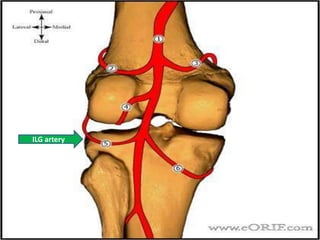

• Blood supply

– medial inferior genicular artery

– lateral inferior genicular artery

AnatomyPopliteal artery

ILG artery

IMG artery

Anatomy • Bloodsupply – medial inferior genicular artery – lateral inferior genicular artery

• #11 Blood supply 1-medial inferior genicular artery supplies peripheral 20-30% of medial meniscus 2-lateral inferior genicular artery supplies peripheral 10-25% of lateral meniscus central 75% receive nutrition through diffusion-This presents a problem when there is an injury to the meniscus, as the avascular areas tend not to heal without the essential nutrients supplied by blood vessels.